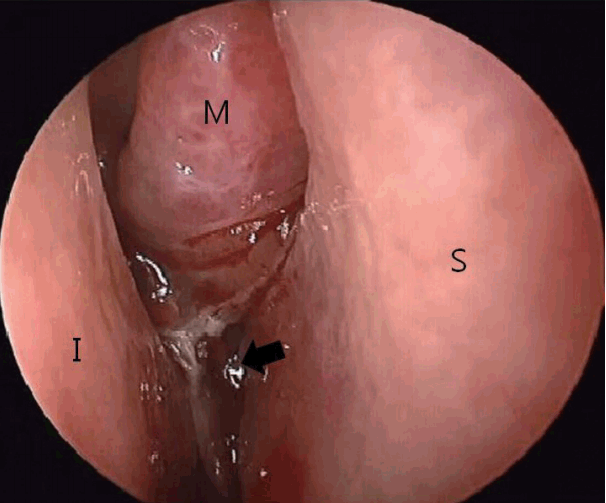

Fig. 2.

Preoperative computed tomography imaging with contrast enhancement. Axial (A) and coronal (B) scans show a low-density soft mass (black arrow) with heterogeneous enhancement between the middle turbinate and inferior turbinate. This mass is also in contact with the right-deviated septum.